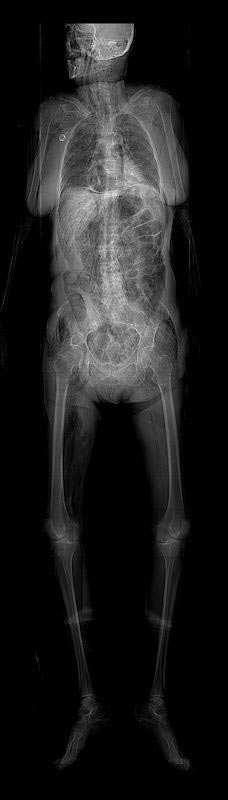

The image below is the scout film of cadaver 33450. Look at the right upper chest, just outside the shadow of the right lung. A small circle of high attenuation (increased radiopacity-whiteness) can be seen just below the clavicle on the right chest. This is the reservoir of a port this patient had put in prior to receiving chemotherapy for metastatic lung cancer.

Now look at the movie file below, which is the CT scan of the same cadaver. Scan down to the chest, paying special attention to the superficial right chest wall. At time= 52, H7, you should see the port's reservoir just beneath the patient's skin. Continue scanning up and down to follow the catheter (in this patient, the catheter loops up and over the right clavicle, and so to follow the catheter in successive cross-sections, you will have to scan up first and then down). Start following the catheter coming off the reservoir at time= 51. Notice how the catheter loops up and over the right clavicle (time= 48) before entering the right internal jugular vein (time= 49, J9). From here, the catheter can be seen following the internal jugular vein to the right brachiocephalic, and then finally the SVC, where the catheter terminates just outside the right atrium.